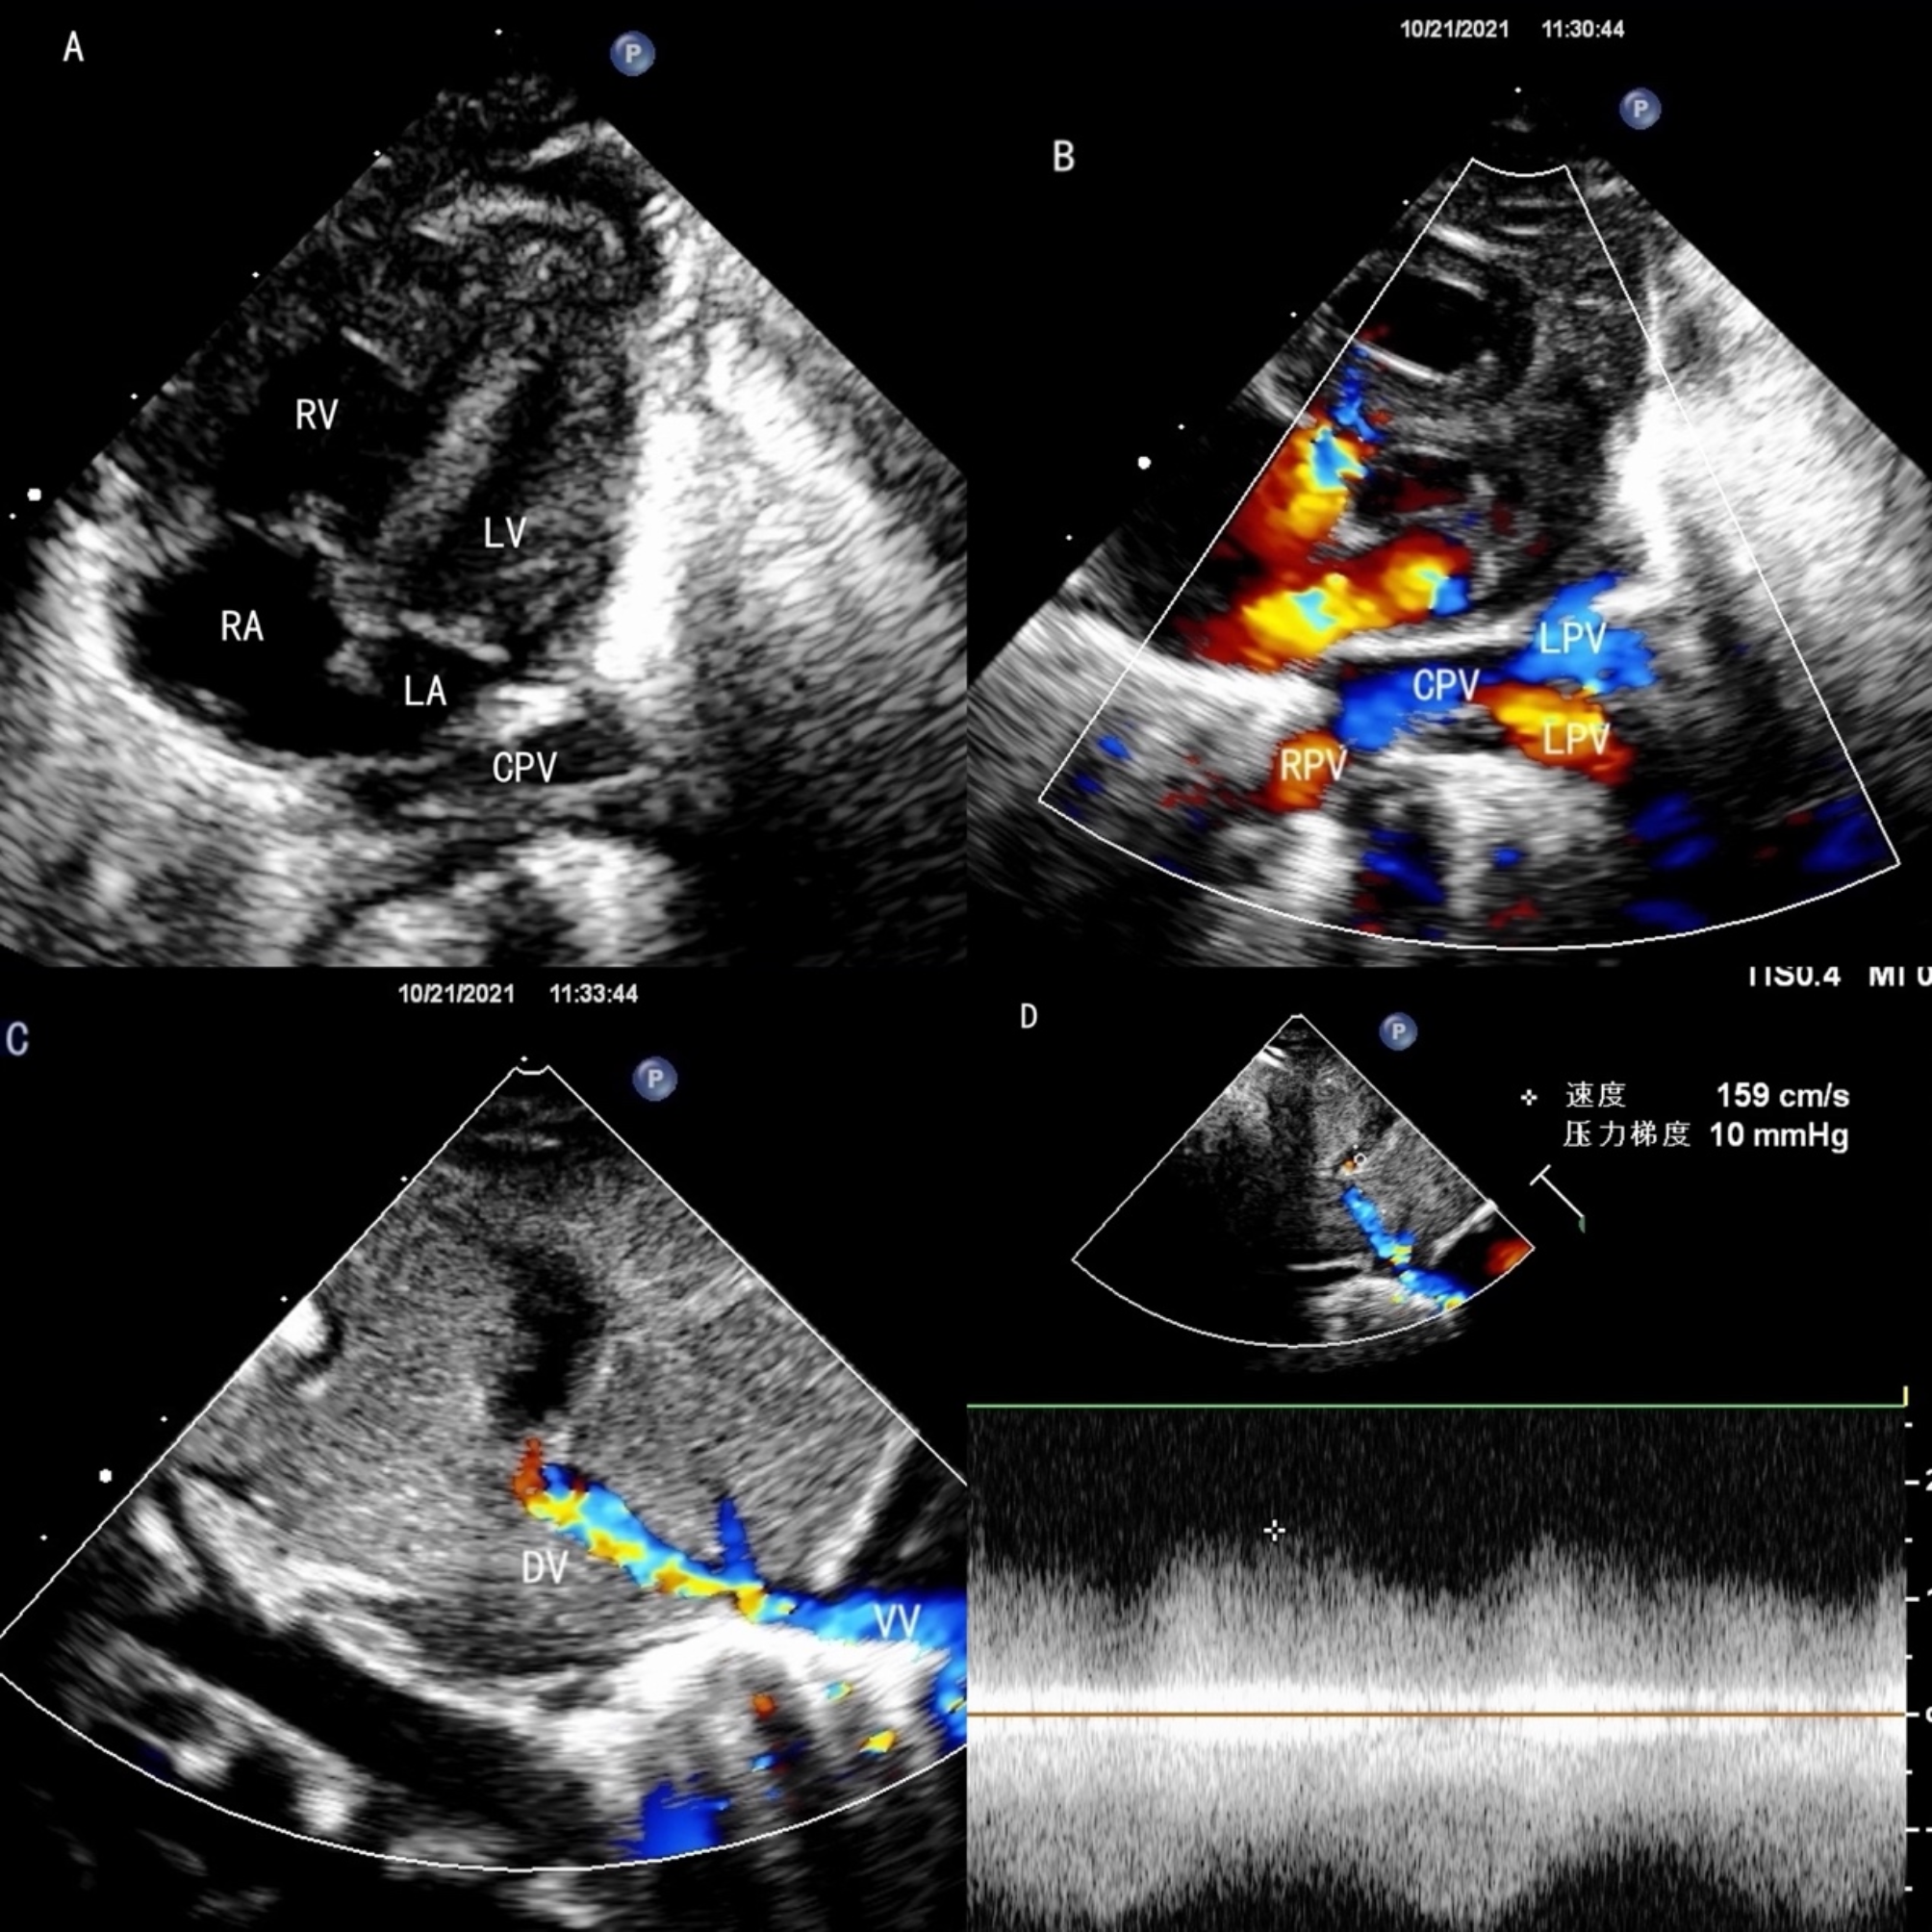

Fig. 3

The echocardiography of infracardiac TAPVC. (A) The left heart is small, the posterior wall of the LA is smooth, and the CPV is behind the LA. (B) The pulmonary veins drain into the CPV. (C) The vertical vein goes down then drains into duct vein, the color doppler shows turbulent flow at the drainage site. (D) A non-phasic flow was detected at the drainage site.